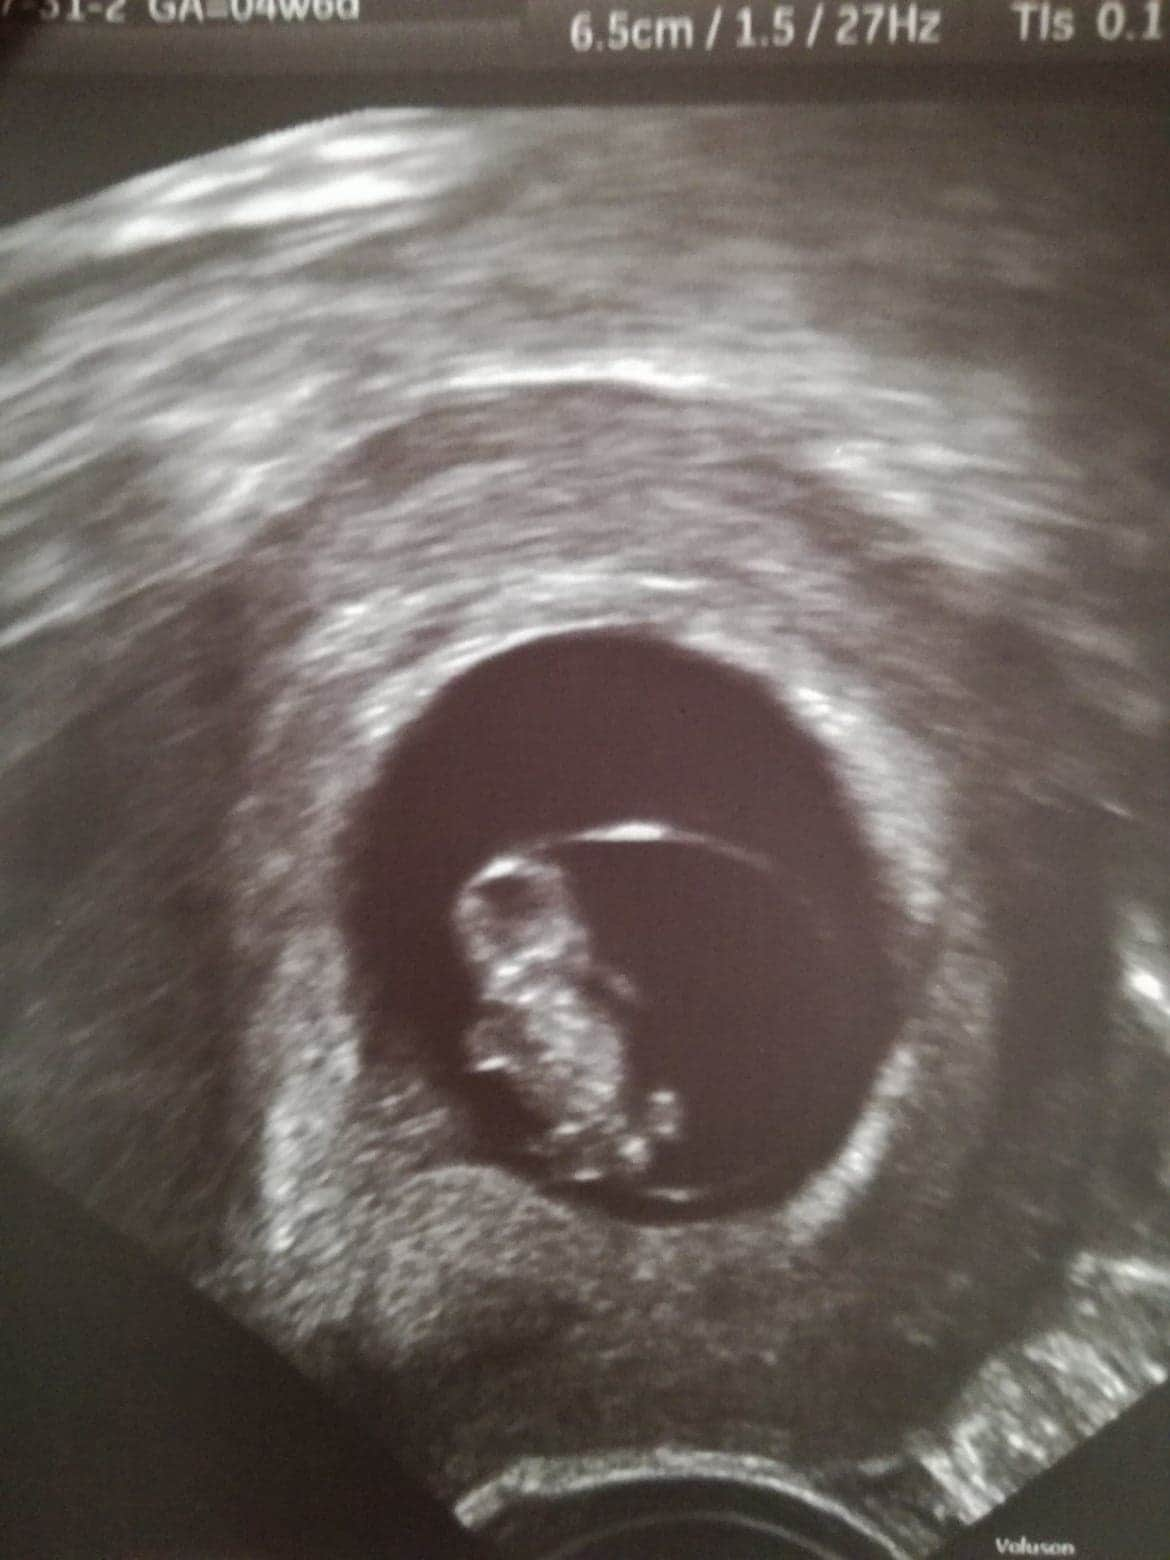

W dniu wczorajszym wypisali mnie ze szpitala. W dniu wczorajszym przebadal mnie sam ordynator który odkrył odwarstwianie kosmówki co spowodowało powstanie małego krwiaka i stąd te plamienia. Kontynuuje Duphaston 3x1 i mam prowadzić oszczędny tryb życia. O powrocie do pracy póki co mogę zapomnieć. Przy wypisie moja dzidzia miała już 9,5 mm i serducho bijące jak dzwon ❤ Chyba nadrabia stracony czas. Za 2 tygodnie kontrola i jako, że ten doktor ma też swoją klinikę będę kontynuować ciążę u niego.

Wrzucam zdjęcie z usg - może Wy potraficie powiedzieć mi gdzie ten krwiak? Szukam szukam i nie wiem...

Też mam krwiaka 12x17mm... na zdjęciu nie widać bo pewnie nie uchwycił go spokojnie musisz się oszczędzać to się wchłonie 😊